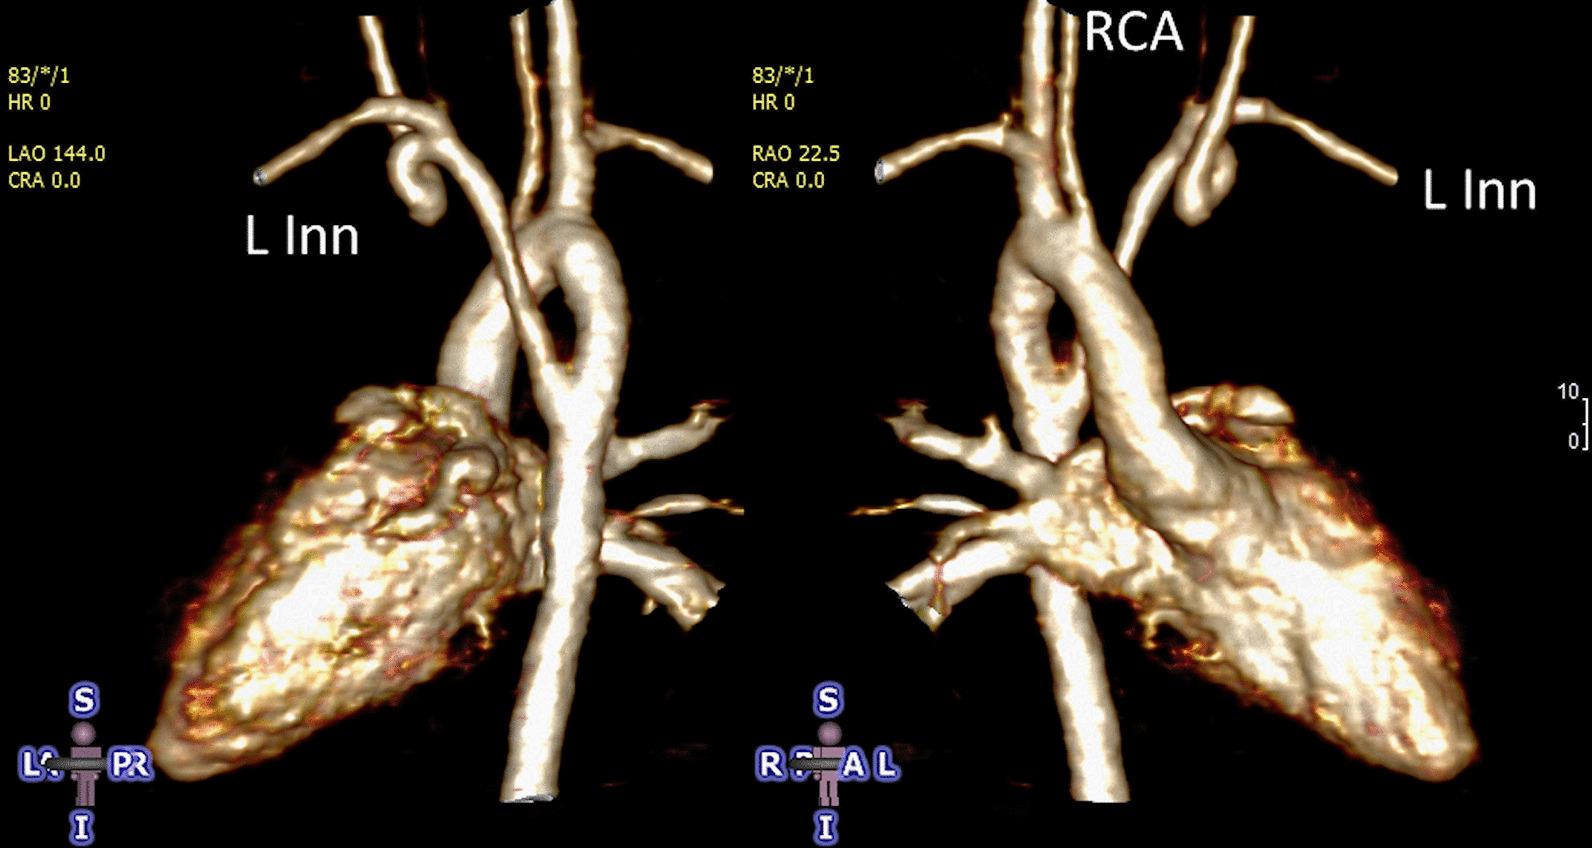

Cardiovascular magnetic resonance (CMR) has been utilized in the management and care of pediatric patients for nearly 40 years. It has evolved to become an invaluable tool in the assessment of the littlest of hearts for diagnosis, pre-interventional management and follow-up care. Although mentioned in a number of consensus and guidelines documents, an up-to-date, large, stand-alone guidance work for the use of CMR in pediatric congenital 36 and acquired 35 heart disease endorsed by numerous Societies involved in the care of these children is lacking. This guidelines document outlines the use of CMR in this patient population for a significant number of heart lesions in this age group and although admittedly, is not an exhaustive treatment, it does deal with an expansive list of many common clinical issues encountered in daily practice.

心血管磁共振(CMR)在儿科患者的管理和护理中已经应用了近 40 年。它已经发展成为评估最小的心脏的宝贵工具,用于诊断、介入前管理和随访。尽管在许多共识和指南文件中提到,但在儿科先天性心脏病和后天性心脏病领域,目前还缺乏一份由众多参与儿童护理的学会共同认可的、最新的、独立的、针对 CMR 使用的大型指南。本指南文件概述了 CMR 在该年龄段的许多心脏病变中的应用,尽管不能说是详尽的治疗方法,但它确实涉及了在日常实践中经常遇到的许多常见临床问题的广泛列表。